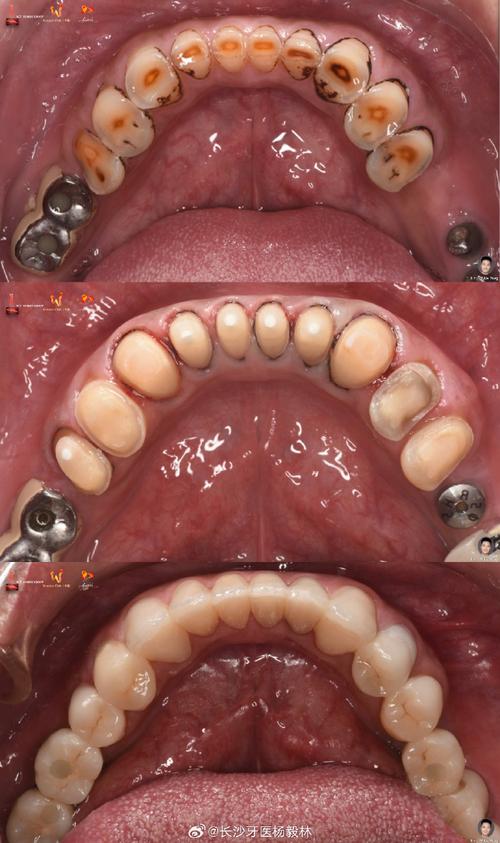

北大口腔马莲修复图片

(图片来源网络,侵删)